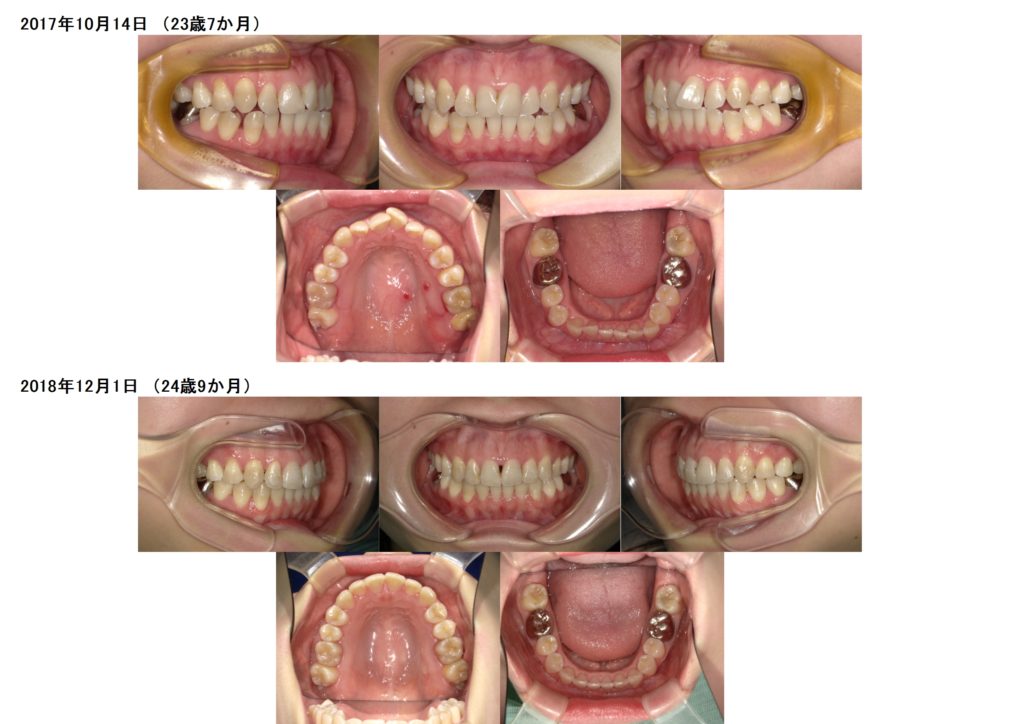

マウスピース矯正 非抜歯治療

今回は非抜歯(抜歯なし)でのマウスピースでの治療例です。

上下顎を適切な数値の形に整えます(精密検査をすると、上下の適正値がわかります)

少し顎の形を整えることによって隙間が少し空いたのが分かりますよね☆

マウスピースをしっかりと真面目に使用していただき、とても早くキレイに治療が終わりました。

上の前歯の歯茎はどうしても初めの歯並びが重なっていたので少し歯茎が腫れていたりとブラックトライアングルが見られます。

少しずつ改善する方も多いので、歯ブラシを優しく丁寧に毎日行って頂くことが大切です☆

(歯周病が進行されている方はどうしてもブラックトライアングルができやすく、抜歯をする方も移動距離が多くなるので、どうしてもリスクはあります)

保定装置もしっかりと使用して頂いている証拠です!!

2年後の保定期間もしっかりと終了しました☆

ブラックトライアングルも良くなってきてますね☆